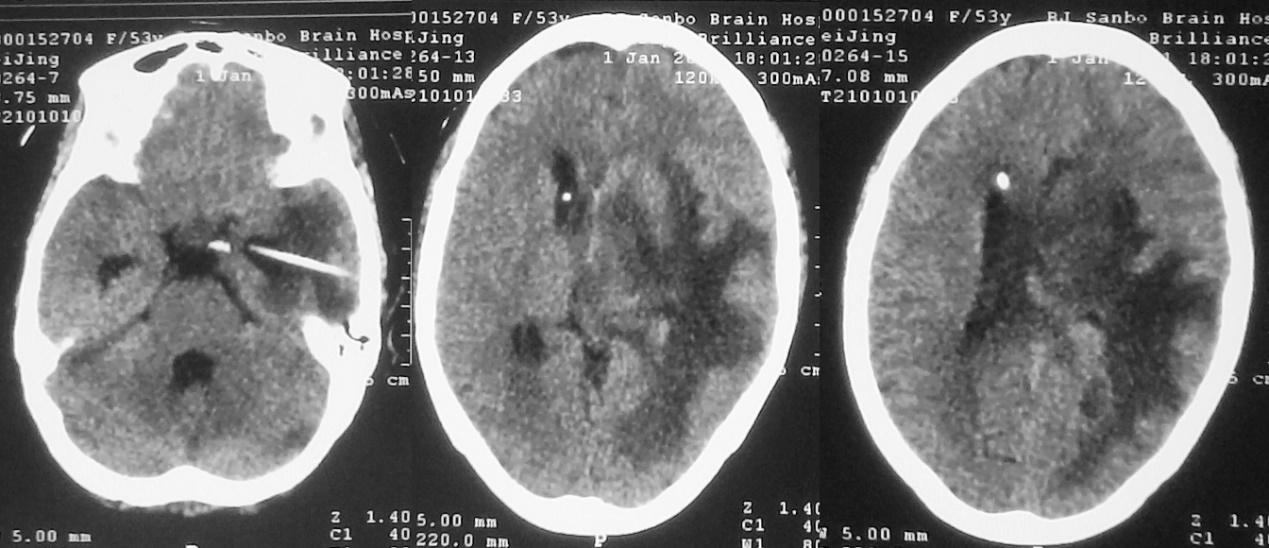

第二次左侧颞角引流术后第1天,即2021年1月1日,患者神志明显好转,清醒,可遵嘱动作,复查头颅CT见各脑室较前均缩小( 图-21 )。

图-21: 2021年1月1日头CT